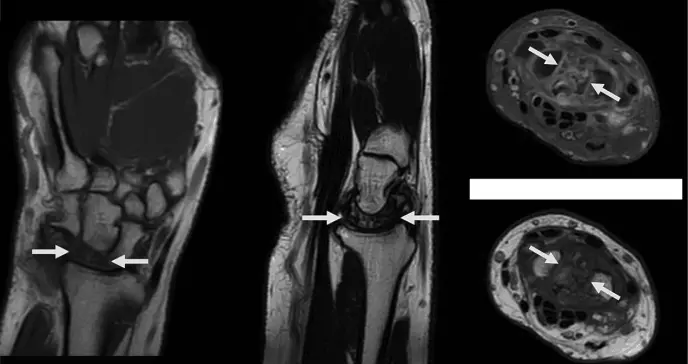

En las secuencias coronales de la resonancia, se apreció hipointensidad difusa y colapso completo del hueso semilunar. Las imágenes sagitales T2 FSE confirmaron una fractura multifragmentaria del semilunar con áreas de esclerosis asociada.

Los cortes axiales con secuencias PD FS permitieron visualizar en detalle la naturaleza multifragmentaria de la fractura y la presencia de osteoedema circundante. Con estos hallazgos, se estableció el diagnóstico de necrosis avascular del semilunar, también conocida como enfermedad de Kienböck en estadio IV según la clasificación de Lichtman, acompañada de artrofibrosis carpiana. Se decidió no realizar resonancia con contraste, ya que el estadio avanzado de la enfermedad no modificaría la actitud terapéutica.

Figura 1. La imagen de RM coronal ponderada en T1 muestra una marcada hipointensidad difusa del hueso semilunar y colapso.

Figura 2. La imagen sagital T2 FSE muestra colapso y fractura multifragmentaria del semilunar asociada a esclerosis. Los hallazgos sugieren cronicidad.

Figura 3. a. La imagen axial PD FS muestra un semilunar multifragmentario asociado con osteoedema. b. La imagen axial T1 muestra un semilunar difuso, hipointensa y multifragmentario debido a cronicidad difusa. Fotos: Caso clínico - Ricardo A Caravantes, Daniela Saenz y Favio Reyna.